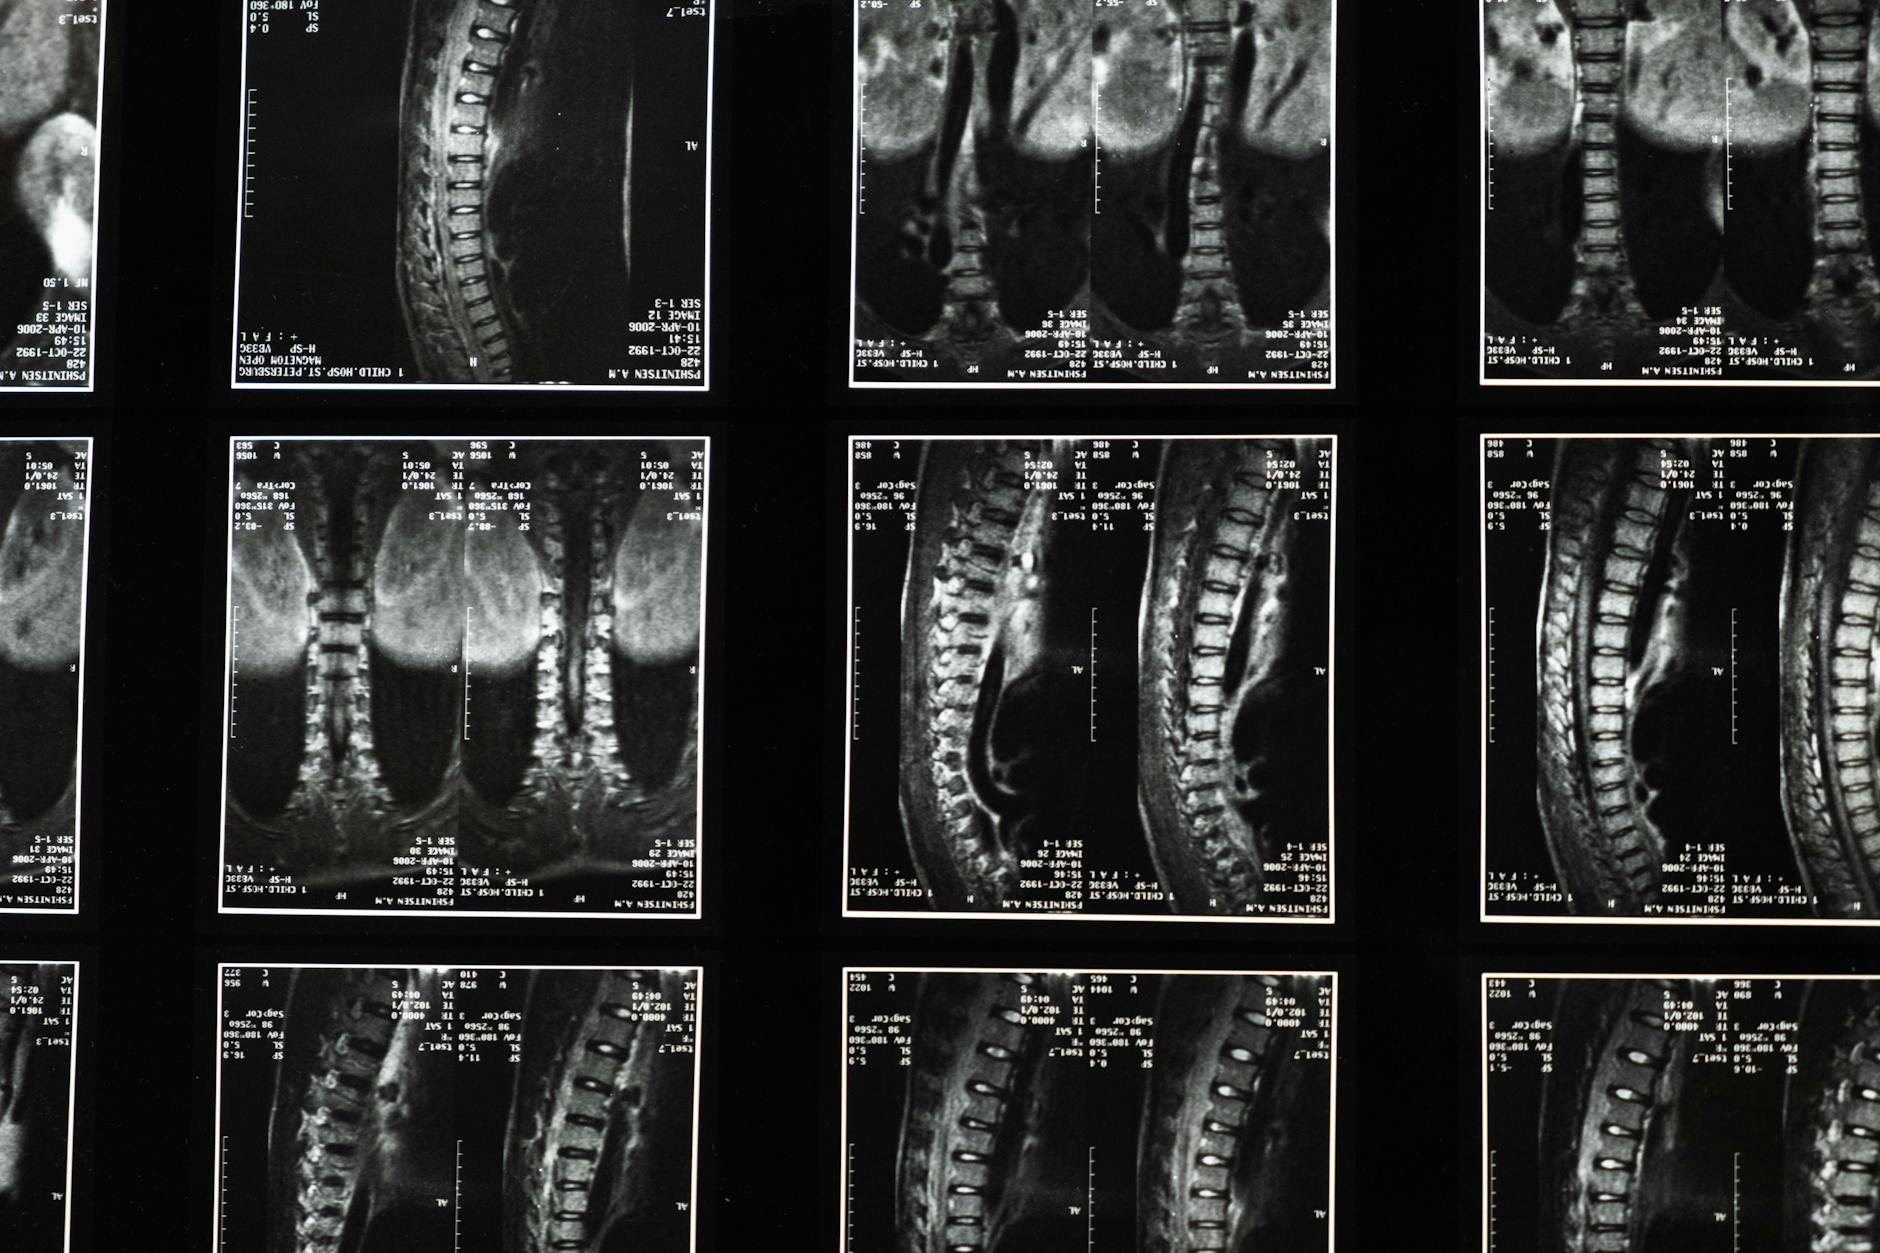

Stomach sleeping flattens the natural curve of the spine and leads to potential long-term issues. The center of the body is the heaviest part and usually sinks deeper into the mattress than the extremities. This uneven weight distribution creates an unnatural arch in the lower back that strains ligaments and muscles. Maintaining a neutral spine is nearly impossible when lying flat on the stomach for eight hours.

Breathing requires turning the head to one side for an extended period which twists the neck vertebrae unnaturally. This severe rotation places immense stress on the cervical spine and the surrounding soft tissues. You may wake up with stiffness or a reduced range of motion after holding this twisted position all night. Persistent neck rotation during sleep can eventually lead to chronic pain or herniated discs in the upper spine.

The gravitational pull on the abdomen causes the pelvis to tilt forward in an anterior pelvic tilt. This position compresses the lumbar vertebrae and stresses the lower back muscles significantly. Many stomach sleepers experience acute morning pain or a dull ache in the lower back region. Alleviating this pressure usually requires switching to a side or back sleeping position to restore proper alignment.

The unnatural twisting of the head and spine can pinch nerves exiting the spinal column. This compression often results in radiating pain or tingling that travels down the arms and legs. Ignoring these neurological signals can lead to chronic conditions like sciatica or carpal tunnel syndrome over time. Relieving this pressure requires a sleep posture that allows the nervous system to rest without impingement.